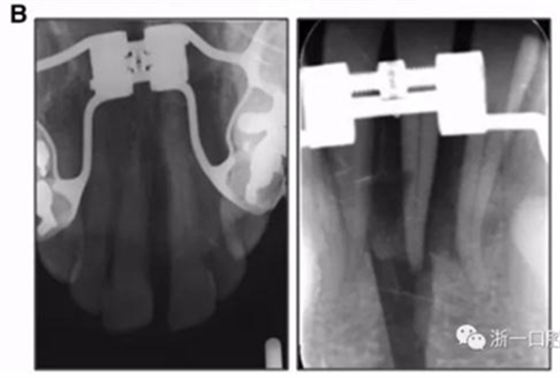

全麻下進行上頜骨腭中縫骨皮質(zhì)劈開及下頜正中劈開術(shù)。手術(shù)后,用X光片檢查上頜骨和下頜骨中線切口的位置和方向。

術(shù)后第9天開始旋轉(zhuǎn)擴弓器,每天轉(zhuǎn)2次,每次轉(zhuǎn)90度,即擴開0.5mm。每隔1周進行檢查,目標上頜擴開9mm,下頜擴開6mm。18天后,上頜中切牙間出現(xiàn)8mm間隙。下頜出現(xiàn)6mm間隙,(于13天出現(xiàn)后,停止旋轉(zhuǎn)擴弓器)。在擴弓器旋轉(zhuǎn)3天后,拍片發(fā)現(xiàn)左下頜中切牙遠中牙根中段有一條低密度陰影,臨床冷熱診反應(yīng)遲鈍,可能為術(shù)中損傷所致。牙體牙髓科會診,建議行根管治療,故行根管治療。